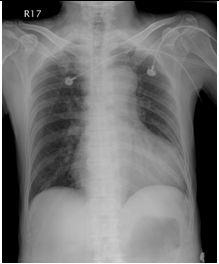

1. 病人62歲,男性,在6月8日清晨6時突然有嚴厲胸疼發生,以致醒來起床,隨即發生冒汗、噁 心、嘔吐及腹痛,乃急往醫院求治。病人有高血壓及貧血病史。理學檢查顯示急病面容,血壓250/100 mmHg,心跳67/min,心肺並無任何異常,但腹部腸蠕動聲減少,而且有腹肌難碰之狀,右腳踝dorsalis pedis脈動消失。胸部X光及心電圖如示。其他影像如圖 。血液檢查,AST 29 U/L;CK 102.0 U/L;CK-MB 22.4 U/L;Troponin I <0.04 μg/L;Amylase 80 U/L;Lipase 32 U/L;Na 3.3 mEq/L;K 3.3 mEq/L;D-dimer 12-24 μg/ml ;BUN 53.6 mg/dl;Creatinine 2.6mg/dl。病人服用Clondine (0.075 mg) 6#bid; Doxazosin (1 mg) 2#hs;Amlodipine (5 mg) 1#bid;Trichlorthiazide (2 mg) 1#qd;Minoxidil (10 mg)2#bid;Valsartan 1#qd; Metoprolol (100 mg) 1/2#qd。請問本病人最可能的診斷是: (A) 急性心肌梗塞 (B) 肺動脈栓塞合併肺動脈高血壓 (C) 急性心衰竭症 (D) 主動脈剝離 (E) 惡性高血壓